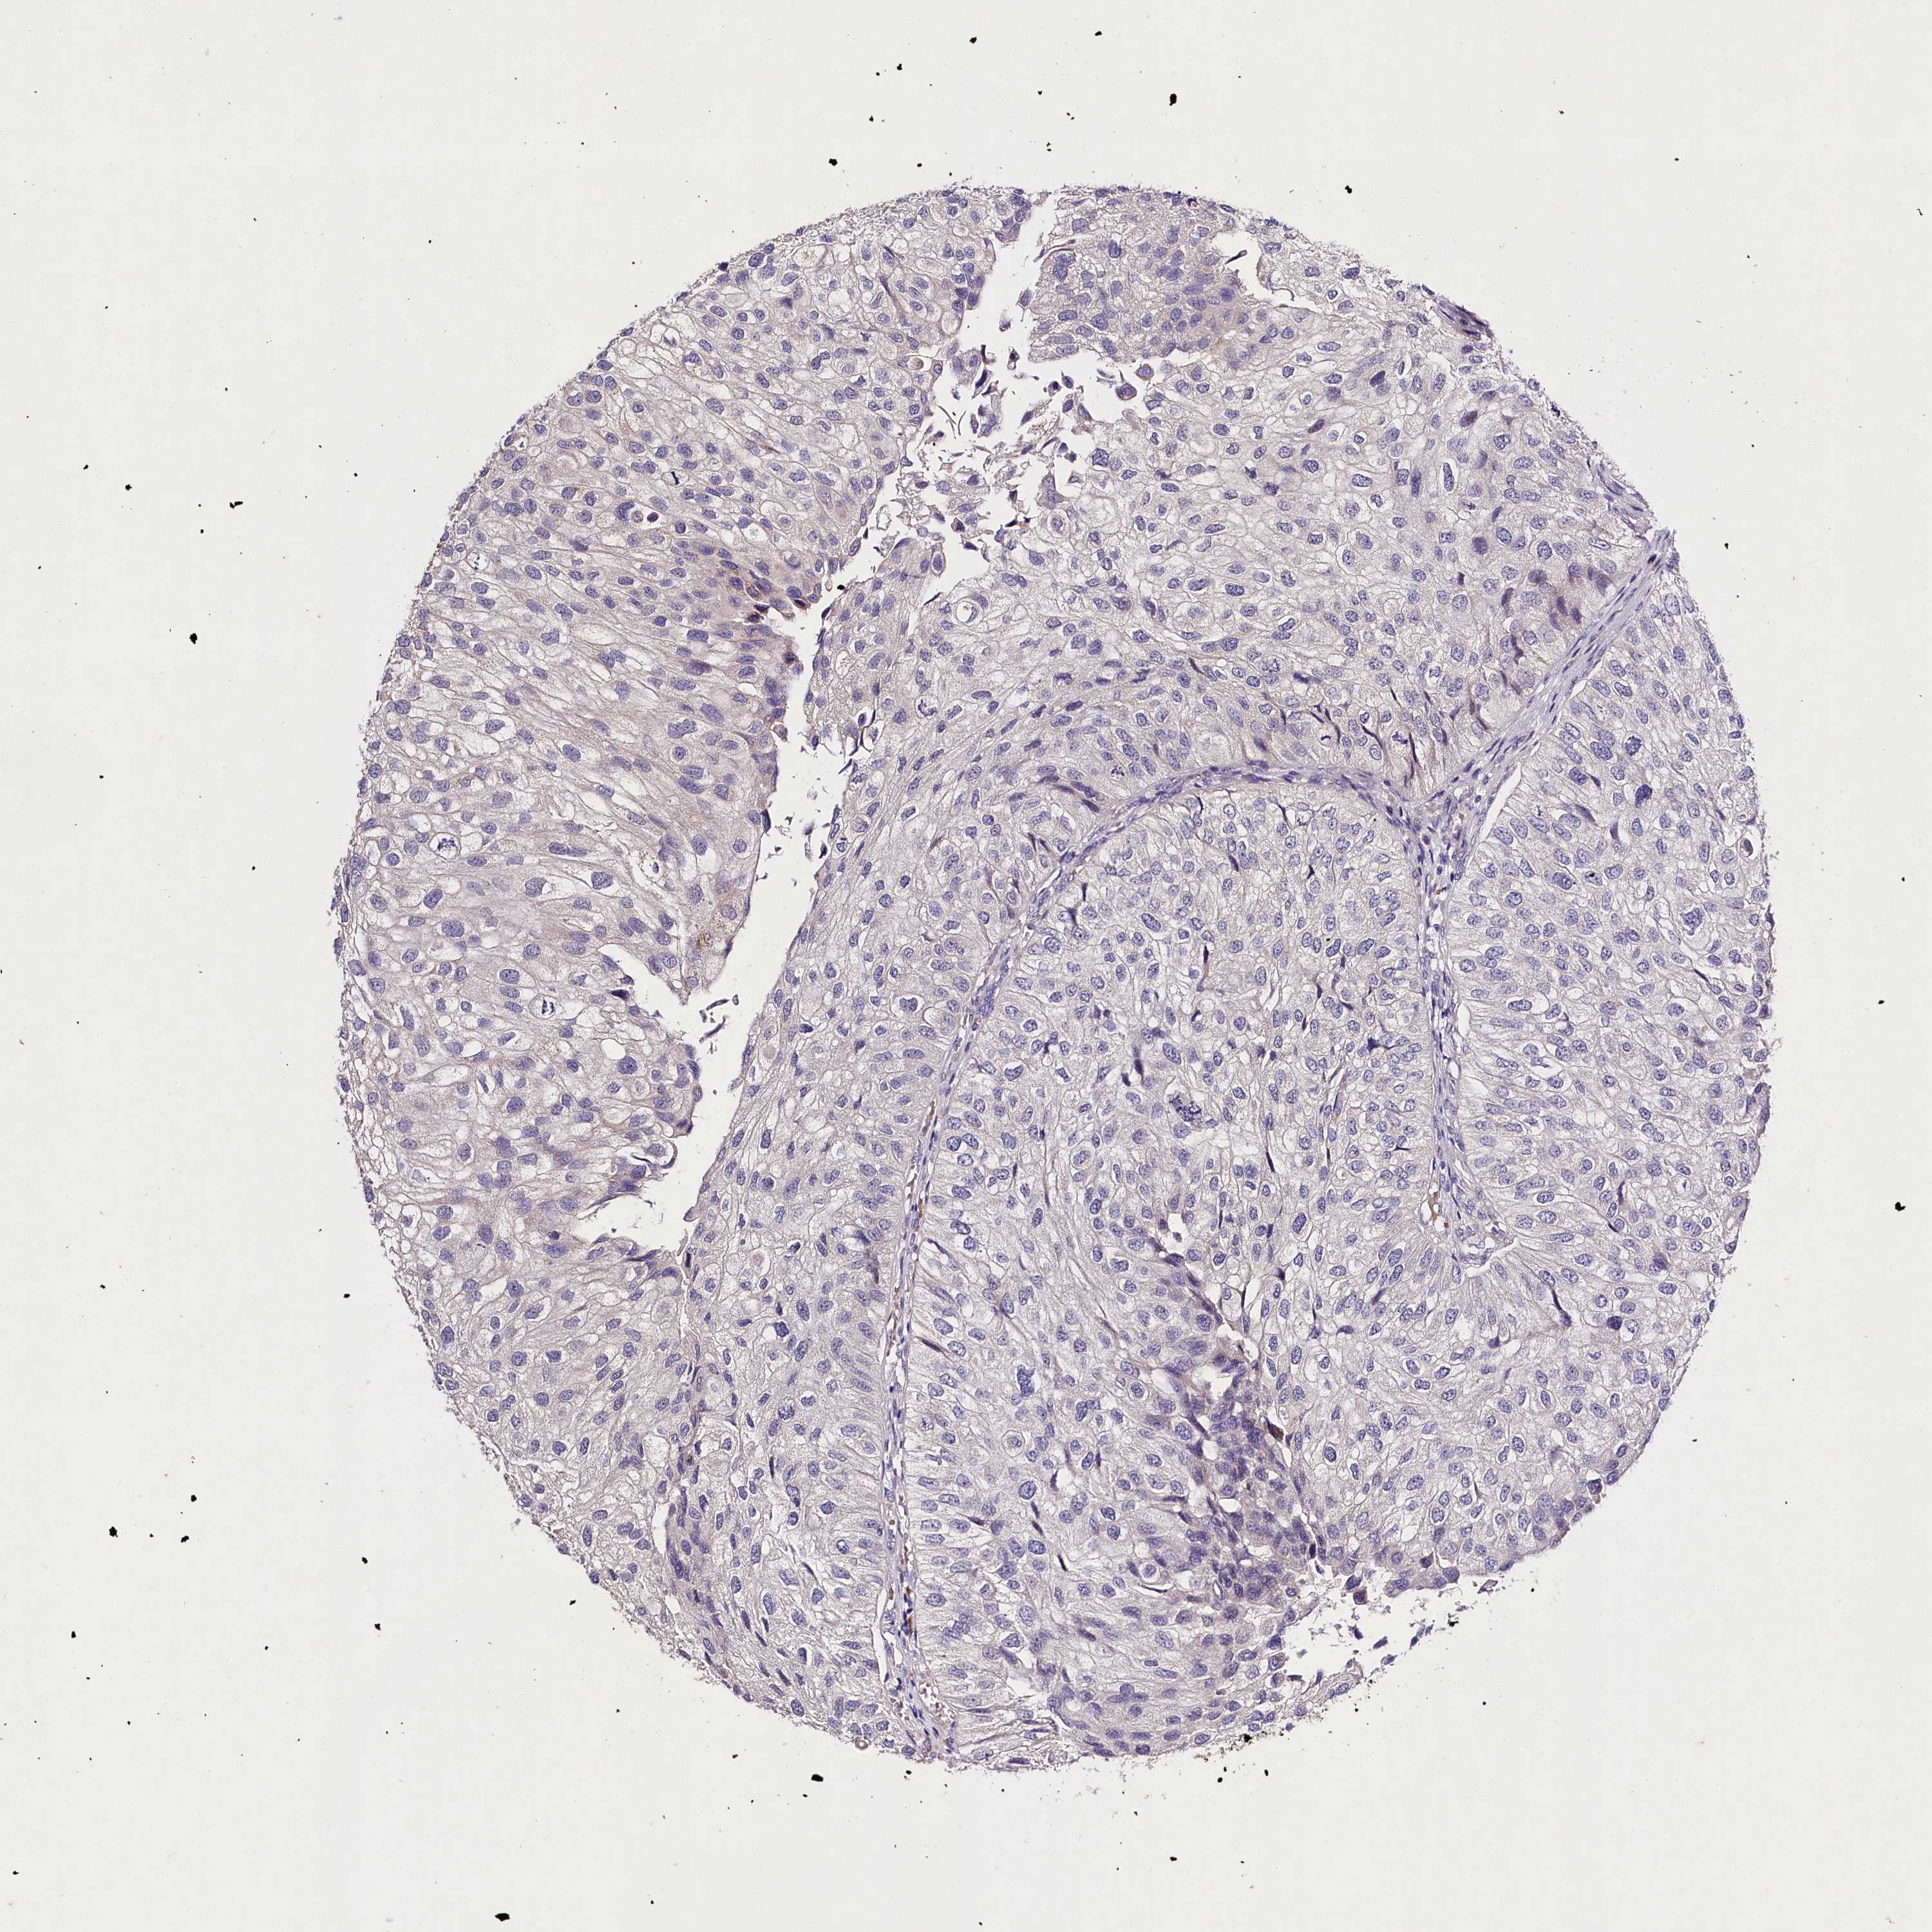

UROTHELIAL CANCER - Protein expressioni

A mouse-over function shows sample information and annotation data. Click on an image to view it in a full screen mode. Samples can be filtered based on level of antibody staining by selecting one or several of the following categories: high, medium, low and not detected. The assay and annotation is described here.

Note that samples used for immunohistochemistry by the Human Protein Atlas do not correspond to samples in the TCGA dataset.

Antibody stainingi

Antibody staining in the annotated cell types in the current human tissue is reported as not detected, low, medium, or high, based on conventional immunohistochemistry profiling in selected tissues. This score is based on the combination of the staining intensity and fraction of stained cells.

Each image is clickable and will lead to virtual microscopy that enables deeper exploration of all samples and also displays staining intensity scores, fraction scores and subcellular localization as well as patient and tissue information for each sample.

Antibody HPA039721

Antibody HPA077838

Urothelial carcinoma, Low grade